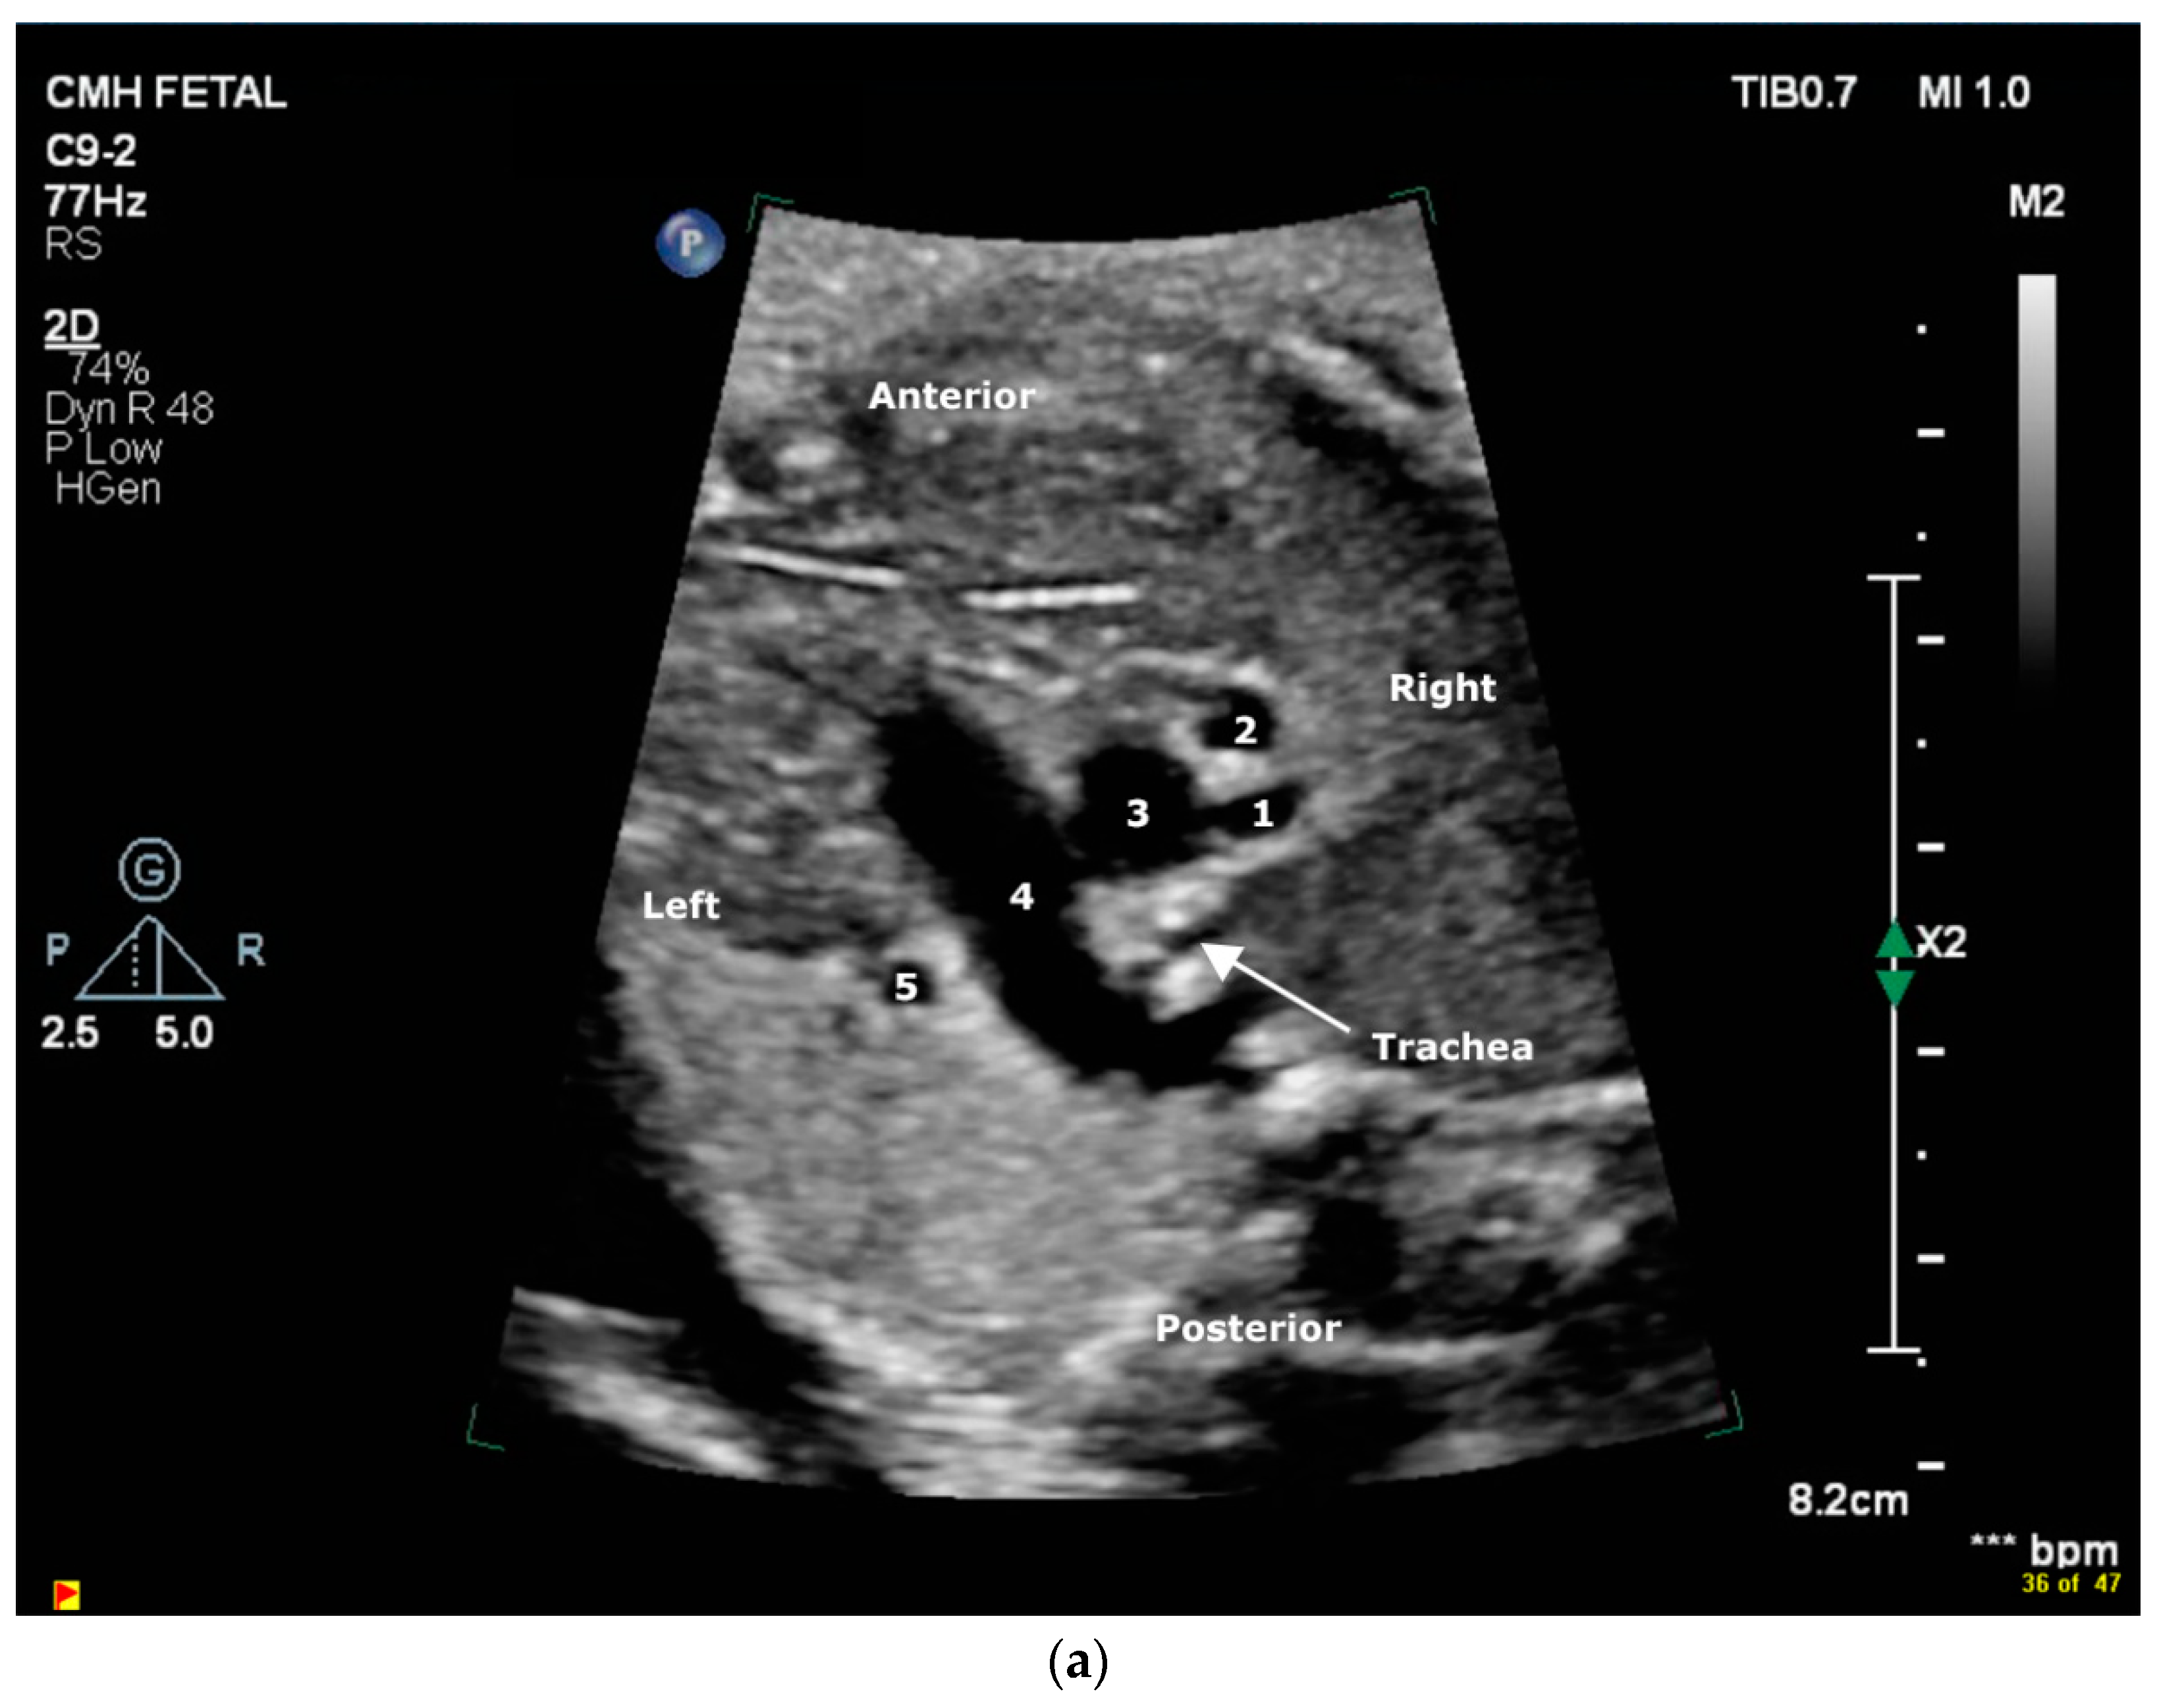

2.1. Case 1